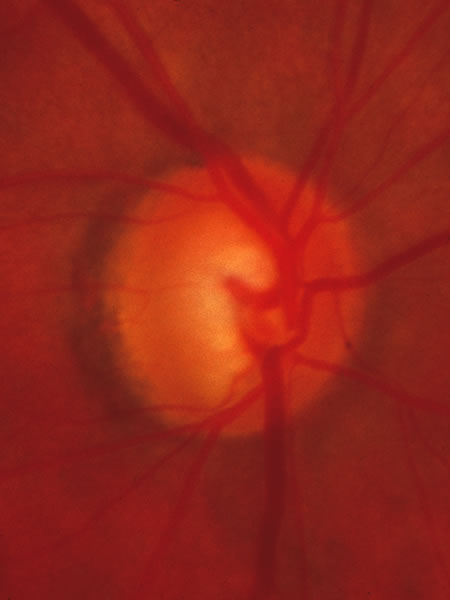

Fig. 37. Swollen optic nerve superiorly during anterior ischemic optic neuropathy caused by giant cell arteritis.

Fig. 38. Same eye after resolution of the attack, with excavation extending to the superior rim of the disc, mimicking the appearance of glaucomatous cupping.